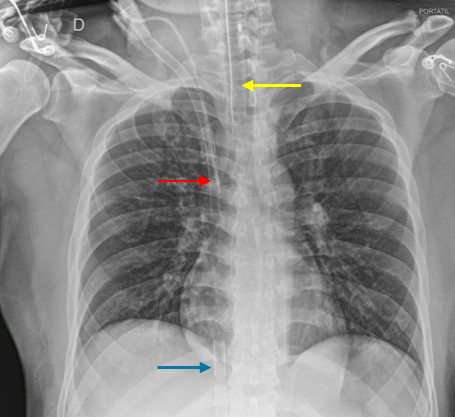

Al ingreso se realizaron estudios de imagen que evidenciaron hiperinsuflación pulmonar sin lesiones parenquimatosas en la radiografía de tórax, motivo por el cual se decidió la instauración de soporte con ECMO VV, mediante cánula de extracción femoral derecha y retorno yugular derecho (ver Figura 1).

Figura 1. Radiografía de tórax tras implante de ECMO. Flecha amarilla: tubo orotraqueal. Flecha roja: cánula de retorno con sangre oxigenada. Flecha azul: cánula de drenaje de sangre no oxigenada